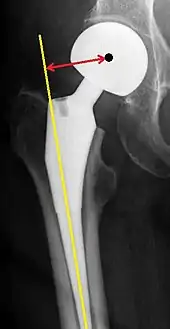

Configuration

Post-operative projectional radiography is routinely performed to ensure proper configuration of hip prostheses.

The direction of the acetabular cup influences the range of motion of the leg, and also affects the risk of dislocation.[9] For this purpose, the acetabular inclination and the acetabular anteversion are measurements of cup angulation in the coronal plane and the sagittal plane, respectively.

Center of rotation: The horizontal center of rotation is calculated as the distance between the acetabular teardrop and the center of the head (or caput) of the prosthesis and/or the native femoral head on the contralateral side.[80] The vertical center of rotation instead uses the transischial line for reference.[80] The parameter should be equal on both sides.[80]